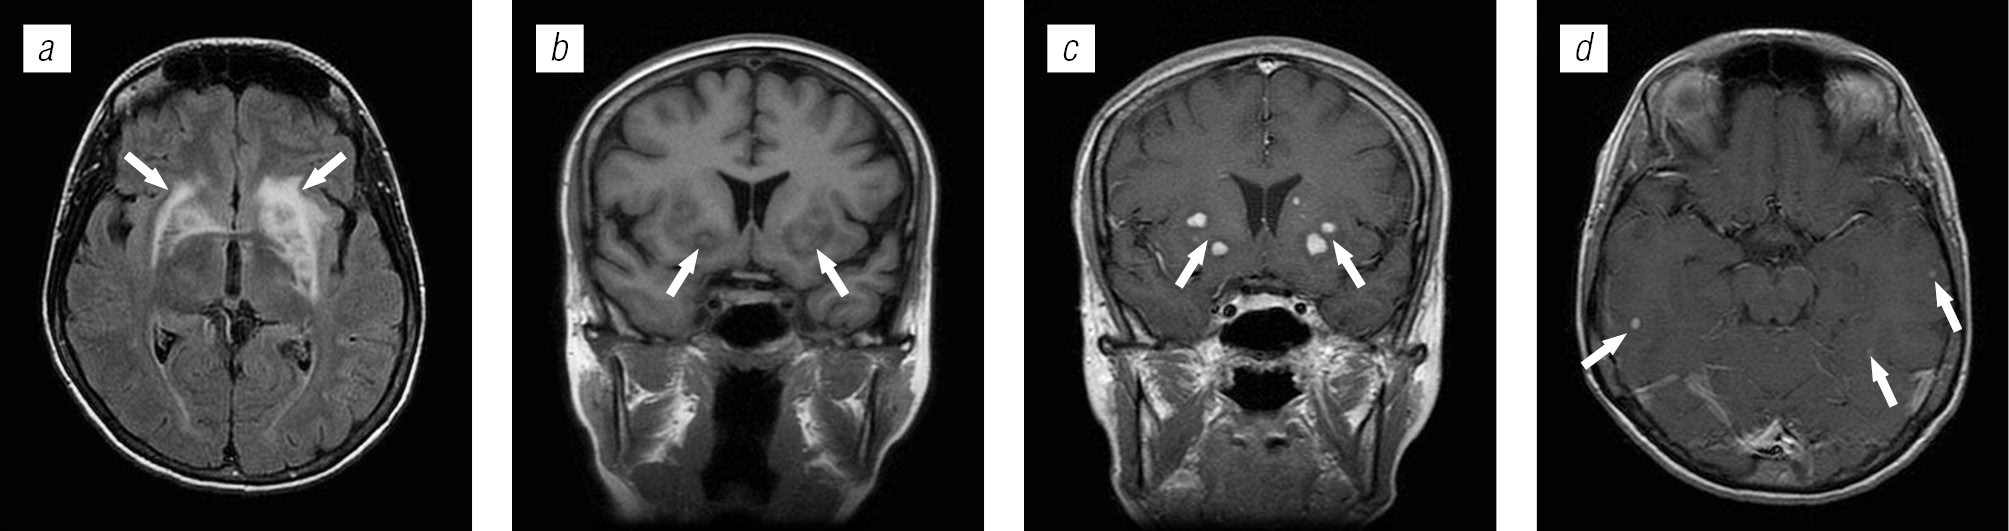

Структура оппортунистических и вторичных заболеваний была представлена токсоплазмозом головного мозга (18,3 %), герпесвирусными поражениями (12,2 %), прогрессирующей мультифокальной лейкоэнцефалопатией (10,24 %), нейроинфекцией неуточненной этиологии (12,2 %), криптококкозом (4,39 %), туберкулезом (2,44 %), лимфомой головного мозга (2,44 %), МАК-инфекцией (0,24 %).